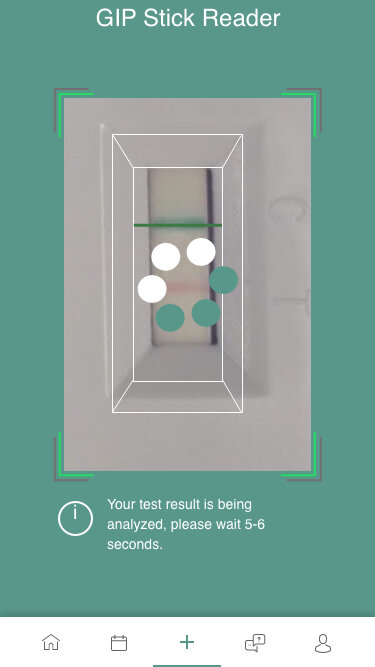

GIP Stick Reader

101